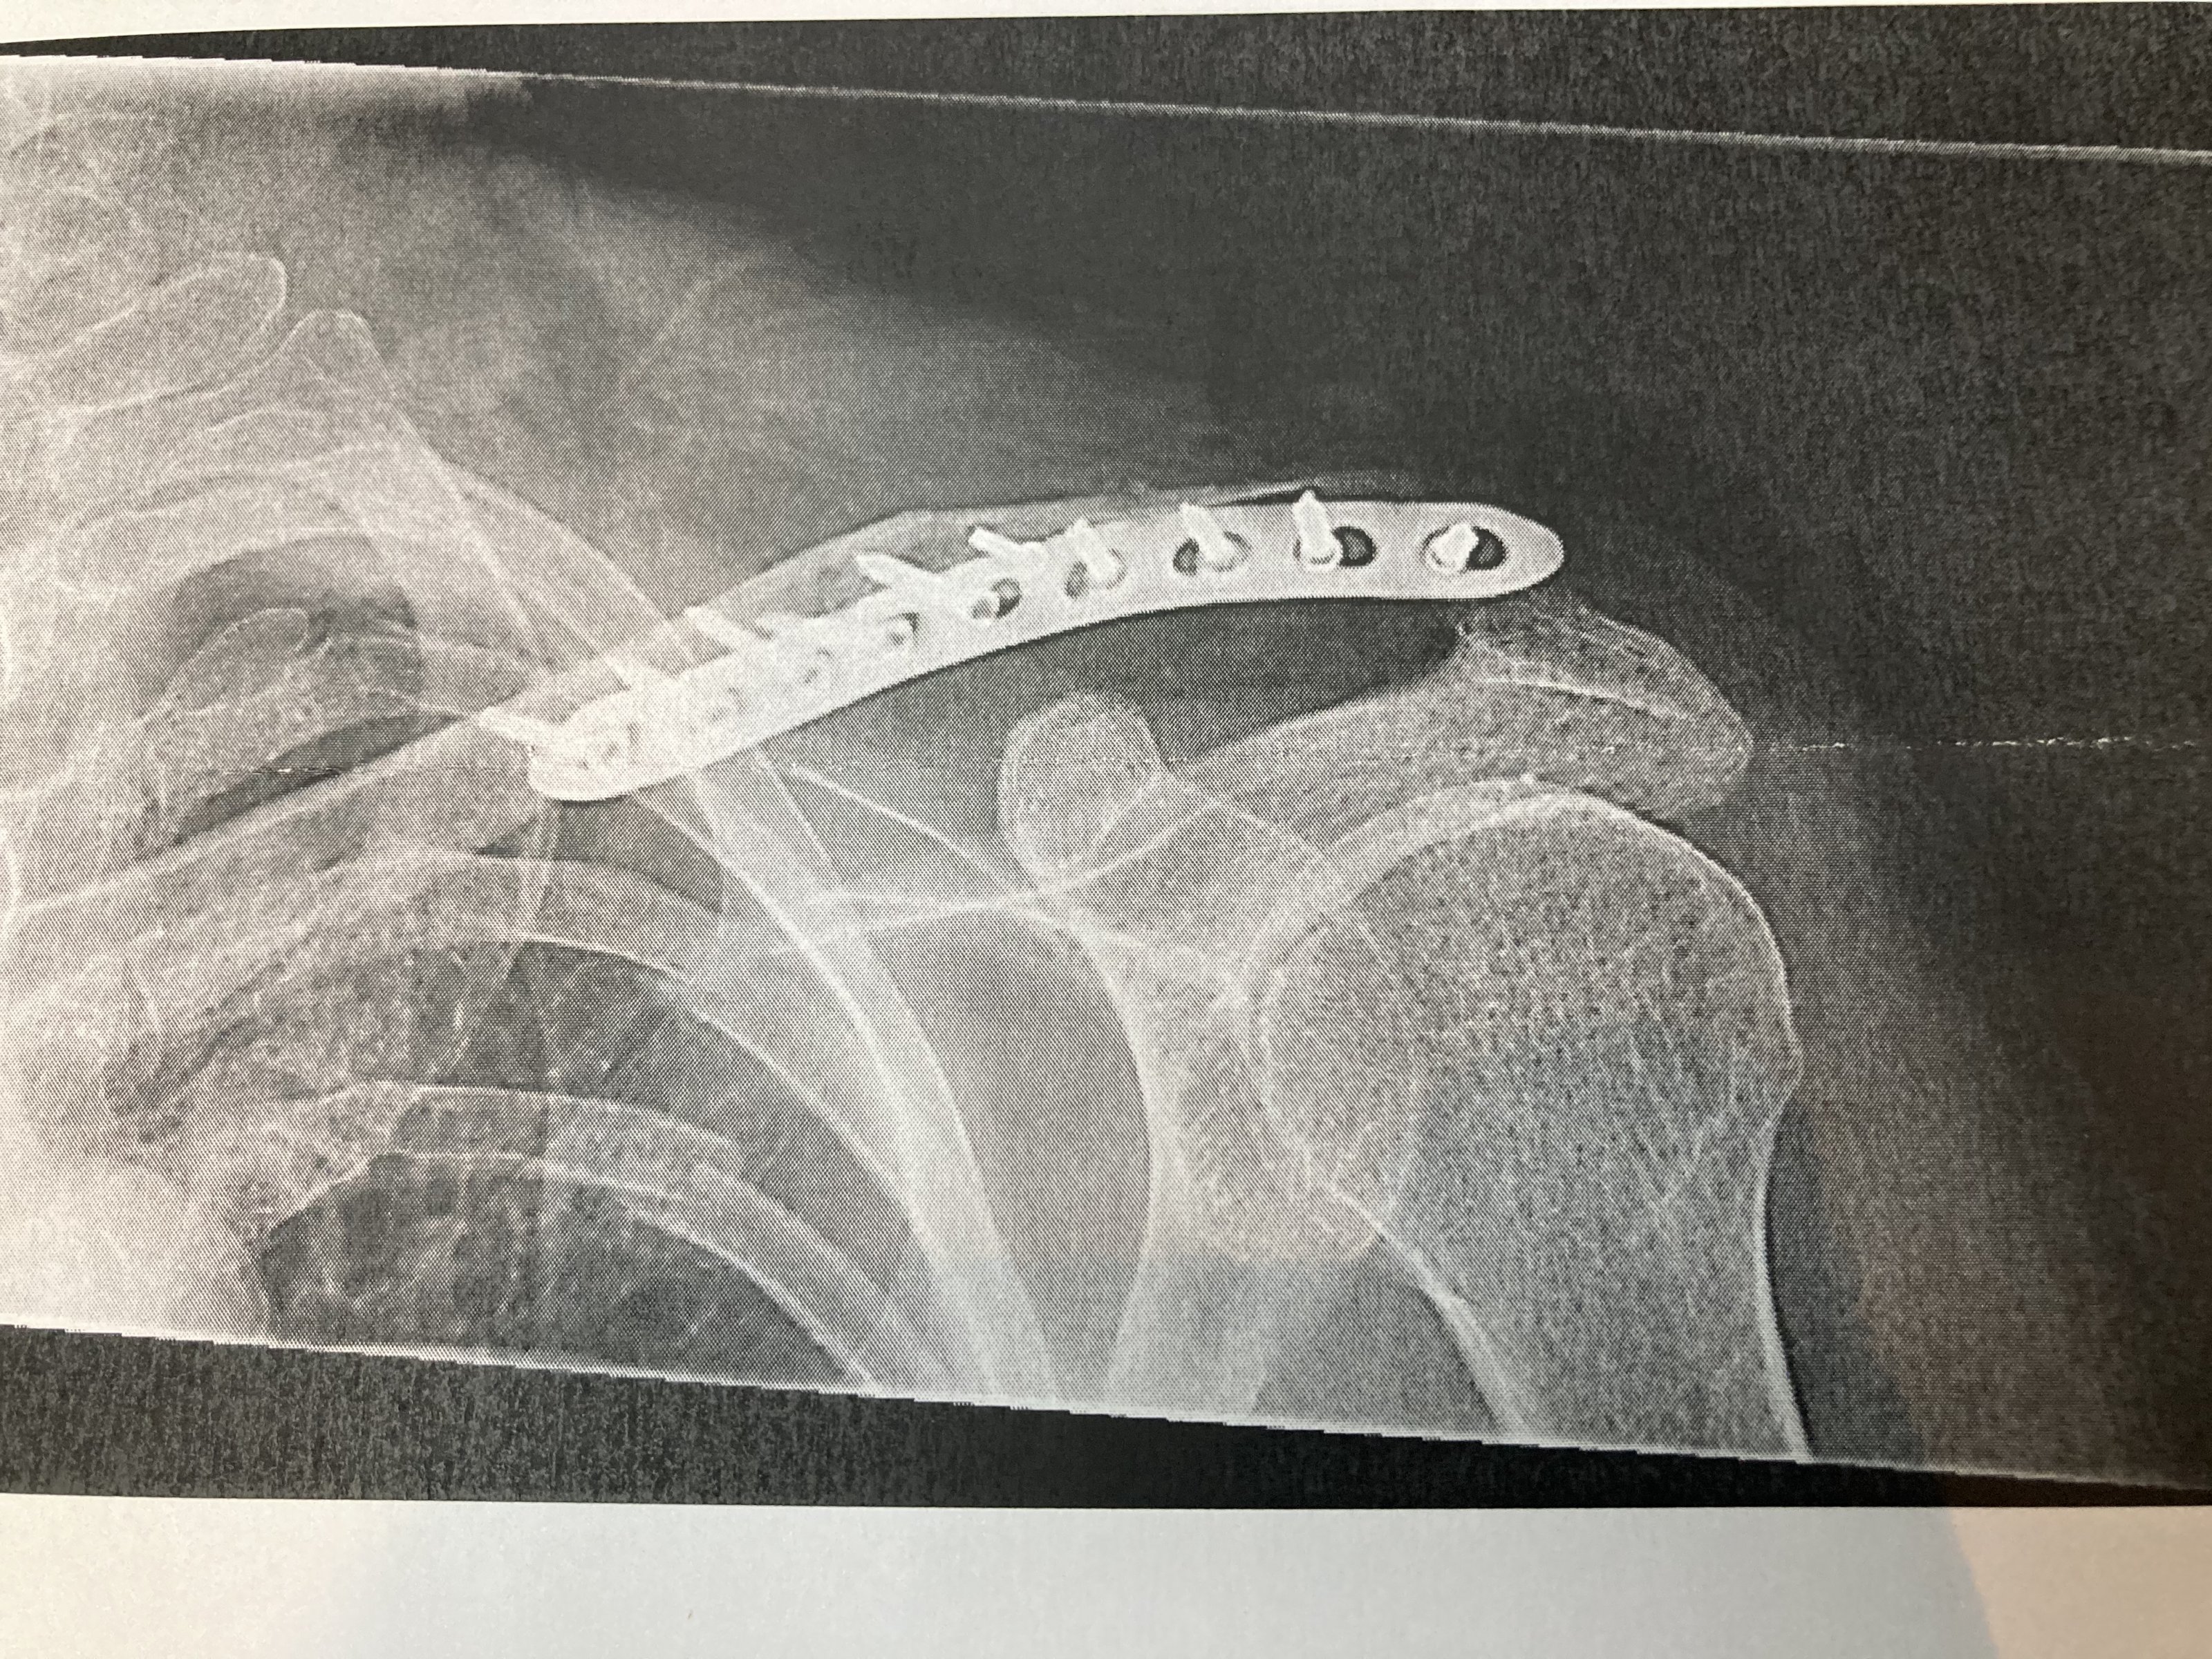

Meine wurde zwar raus genommen wie oben gesehen aber gleich ersetzt mit noch mehr Schrauben. Die erste ist ausgerissen. Hier die neue. Habe ich diese Woche Dienstag gekauft. ;-)Meine Bonebridge is noch drinAnhang anzeigen 444429